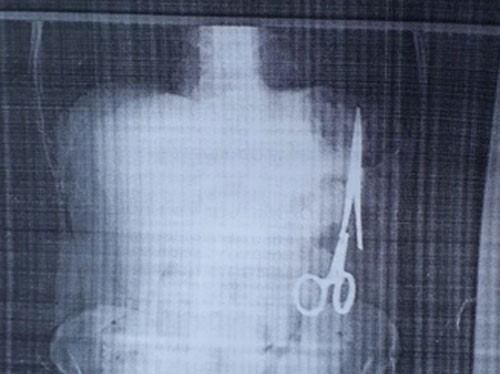

Chiếc kéo nằm trong bụng ông Nhật từ năm 1998. (TTXVN)

Kéo được lấy ra ngoài hôm thứ Bảy vừa qua. (TTXVN)

Ca mổ cho bệnh nhân Ma Văn Nhật bắt đầu lúc 12 giờ 30 trưa và kết thúc sau gần 3 tiếng đồng hồ. Chiếc kéo (panh phẫu thuật) nằm ở bên trái ổ bụng, sát đại tràng, dài 15 cm đã được lấy ra khỏi bụng bệnh nhân.

Bác sĩ cho biết phần tay cầm của kéo bị hoen rỉ nhẹ, chọc thủng vào đại tràng của bệnh nhân nên các bác sĩ phải khâu nối đại tràng cho bệnh nhân. Sau ca giải phẫu, bệnh nhân hồi tỉnh, sức khoẻ diễn biến theo chiều hướng tốt. Dự tính khoảng 10 ngày nữa, bệnh nhân sẽ được xuất viện.

Kết quả siêu âm ngày Giáng Sinh 25 tháng 12 cho thấy trong ổ bụng của ông có một chiếc kéo dài khoảng 15 cm, được cho là chiếc panh chuyên dùng để mổ của ngành y. Hai ngày sau, ông đến siêu âm tại BV Bắc Kạn và họ cũng thấy kết quả tương tự.